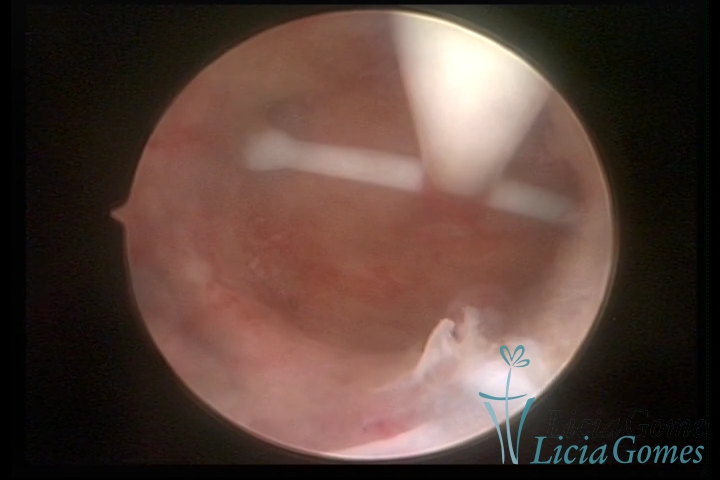

Canal cervical com fio do DIU